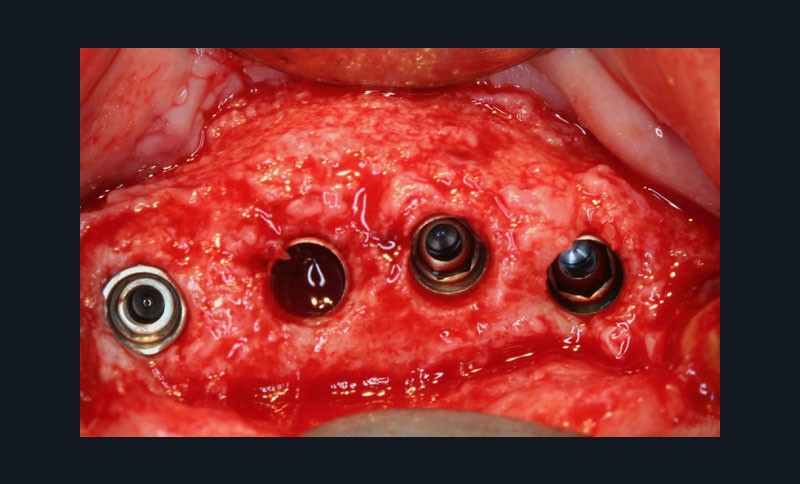

La troisième approche consiste à libérer les lambeaux afin d’obtenir la laxité nécessaire à une fermeture sécurisée du site augmenté. Le relâchement du lambeau lingual décollé jusqu’à la ligne oblique interne est obtenu par un « brossage » apico-coronal de sa face interne à l’aide d’instruments spécifiques. Celui du lambeau vestibulaire repose sur le même principe (soft brushing). Les sutures finalisent la procédure en répartissant les tensions de repositionnement des lambeaux à distance (apical matress) et à proximité des berges de l’incision crestale. Le port des prothèses adjointes est prohibé et les sutures sont déposées 4 à 5 semaines après la chirurgie. Lors de la mise en place des implants (environ 4 mois après l’augmentation osseuse), le Docteur Surménian applique le principe de limitation de la compression des tissus durs en surdimensionnant son ostéotomie (surtout au niveau cortical). Ce principe l’a amené à sélectionner un implant (Anyridge® de Megagen) présentant une stabilité primaire majorée sans pour autant rechercher une élévation du couple d’insertion (signe de compression tissulaire).